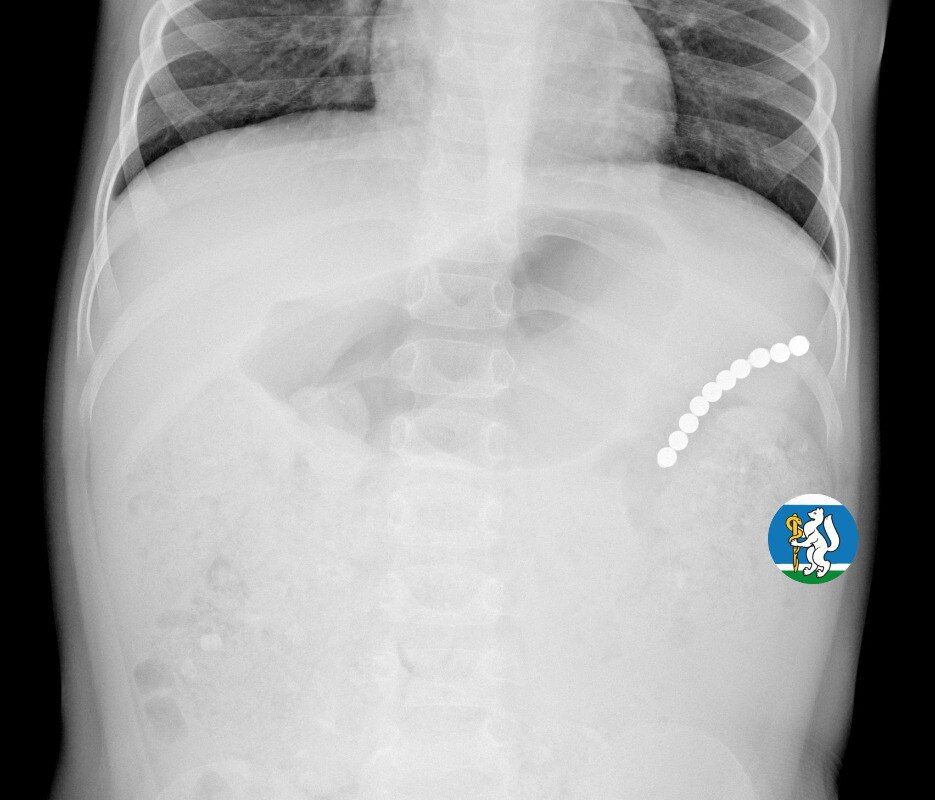

Девочка рассказала родителям о плохом самочувствии, и те показали ее врачам. Медики направили пациентку на рентген грудной клетки. Благодаря обследованию специалисты обнаружили в проекции желудка цепочку магнитов, соединенных между собой. Ребенку сразу же госпитализировали и оказали помощь.

«Для минимизации риска осложнений удаление инородных тел было проведено интраоперационно. В ходе вмешательства дежурная бригада врачей извлекла 10 магнитных шариков, цепочка которых в длину составила 5 сантиметров», — рассказал детский хирург ДГКБ №9 Андрей Чукреев.